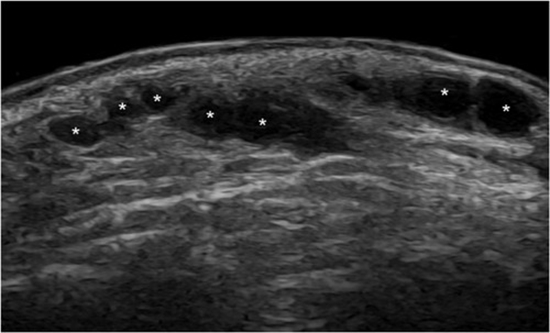

Results: Filler-pattern ultrasound is material-specific: HA-anechoic/hypoechoic, pseudocystic deposits; PLLA-initially hyperechoic, fading over time; PCL-a hypoechoic matrix with hyperechoic comet-tail spots; PMMA-bright echogenic deposits with comet-tail artifacts; CaHA-echoes/shadows depend on dilution/mixing; PAAG-mostly anechoic/hypoechoic and stable over time; silicone-distinctive snowstorm/posterior reverberation; autologous fat-hypoechoic nodules with possible fat necrosis. Vascular occlusion shows absent/reduced Doppler flow; Cellulitis/panniculitis show increased echogenicity, thickened septa, and edema; abscess is an anechoic/hypoechoic lesion with debris and posterior enhancement. Granulomas are hypoechoic nodules with possible calcifications or vascularity. Fat necrosis presents as oil cysts (round anechoic deposits with echogenic borders; calcifications possible). Migration is filler in abnormal locations; overfilling denotes accumulated filler; capsular contracture shows as hyperechoic capsule surrounding deposits.